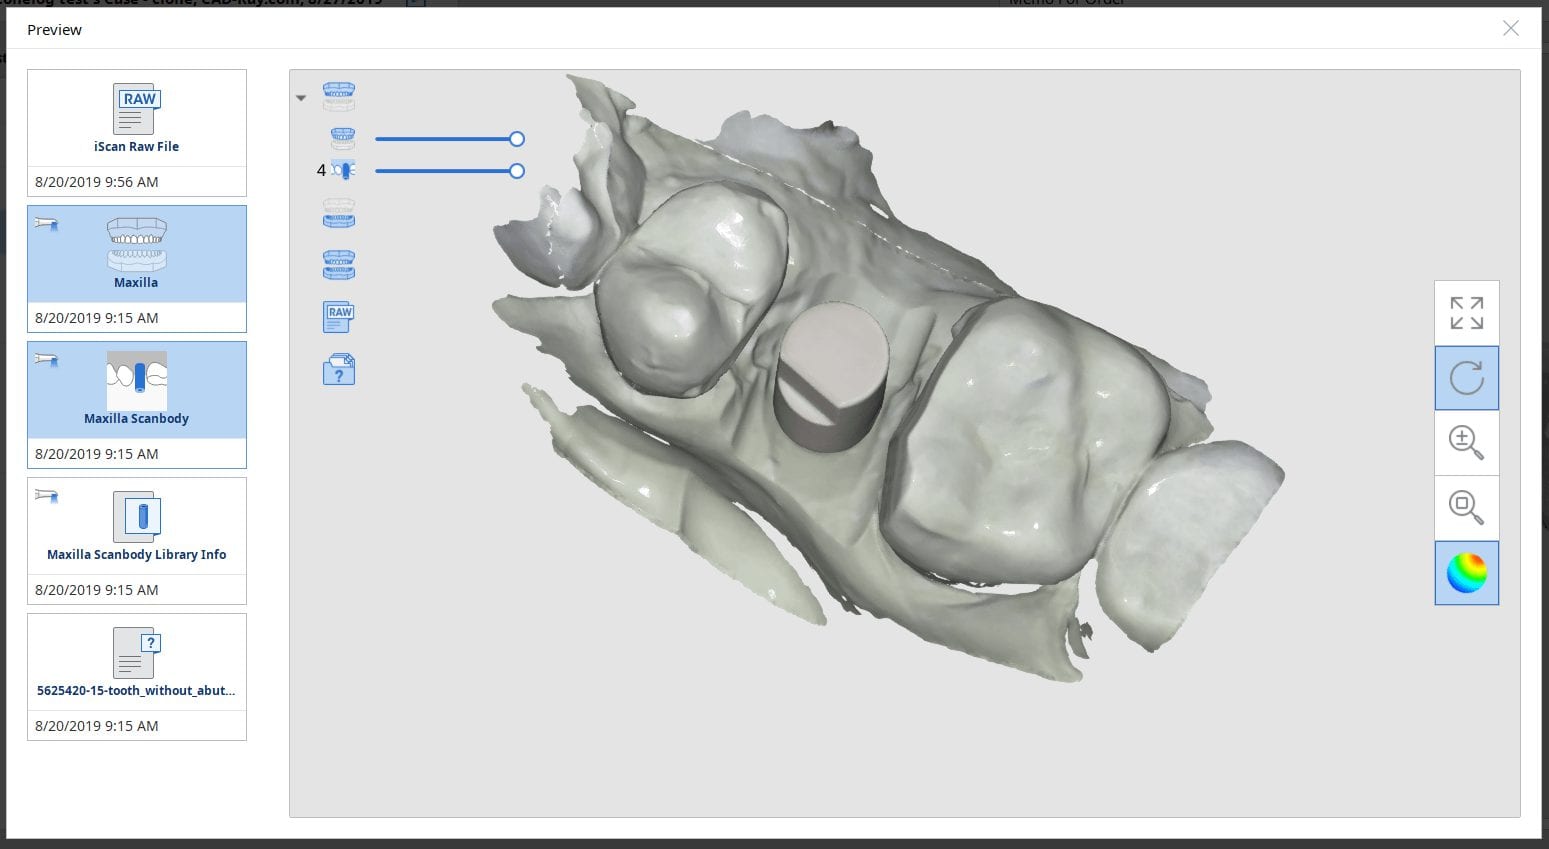

August 22, 2019A new feature coming to Medit i500 is the automatic detection of scanbodies while you are imaging. In this clinical case, two implants are placed in the lower left quadrant […]